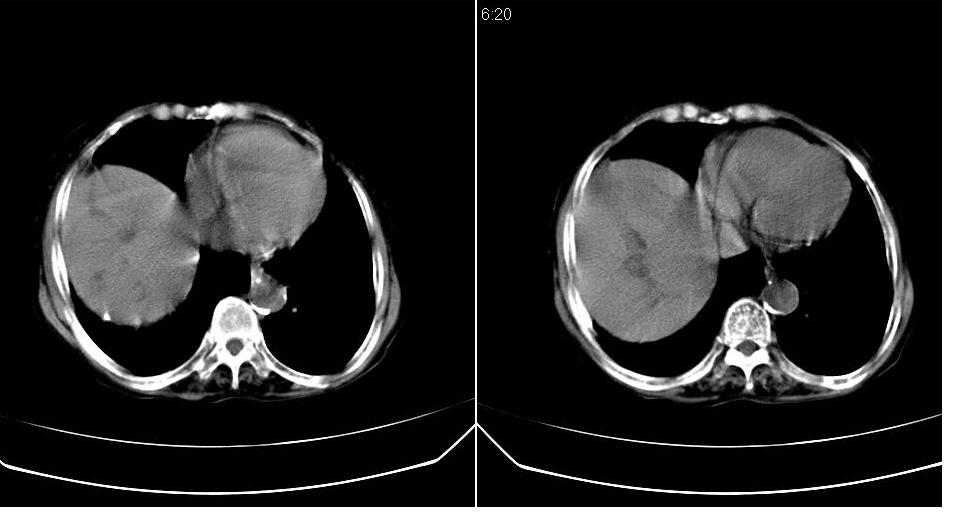

标题: CT23701:上腹部CT平扫

女 76岁,腹痛十余天。